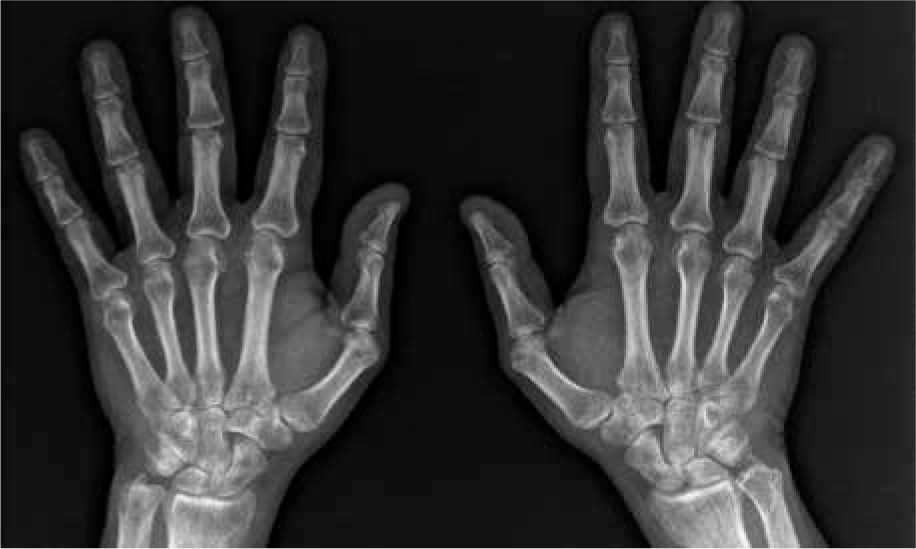

Fig. 2

X-ray of hands showing juxta-articular osteoporosis and inflammatory cysts. No erosions and joint space narrowing. Sharp/van der Heijde score = 0. Juxta-articular osteoporosis is a typical finding in hand X-ray in RA but rare in AS

Here, we describe a case of a 52-year-old man with long-standing ankylosing spondylitis (AS) with bilateral ankylosis of the sacroiliac joints, grade IV according to modified New York criteria (Fig. 1) with a history of peptic ulcer disease and no other comorbidities who developed seropositive rheumatoid arthritis (RA). The diagnosis of AS was made in 2006 and was based on a combination of inflammatory back pain, X-ray of the sacroiliac joints (bilateral grade III sacroiliitis at the time of diagnosis) and the presence of HLA-B27. He did not present peripheral arthritis, enthesitis, uveitis or psoriasis. At the time of diagnosis, inflammatory indicators were increased: C-reactive protein (CRP) 9.8 mg/l (normal value [NV] < 5 mg/l), erythrocyte sedimentation rate (ESR) 48 mm/h (NV < 12 mm/h]) but rheumatoid factor (RF) and anti-citrullinated peptides antibodies (ACPA) were absent. Baseline disease activity measured with Bath Ankylosing Spondylitis Disease Activity Index (BASDAI) was high: 8.6. Initially, the patient was treated with non-steroidal anti-inflammatory drugs (NSAIDs) for 6 years. Since NSAIDs ceased to control the disease activity in 2012, etanercept was introduced. He had undergone left (2013) and right (2014) hip arthroplasty due to severe secondary coxarthrosis in the course of AS. Because of worsening of spinal pain and stiffness, significant deterioration in mobility, and persistent systemic inflammation (ESR 52 mm/h, CRP 102 mg/l) etanercept was replaced with secukinumab in January 2020. In February 2020, after two doses of secukinumab, the patient was admitted to the tertiary rheumatology center with acute symmetric polyarthritis of new-onset involving shoulders, elbows, wrists, small joints of the hands, feet, and knees with pain scored 10/10 on the Visual Analogue Scale (VAS). Inflammatory indicators were increased: CRP 35 mg/l, ESR 73 mm/h. X-rays of the hands and feet did not reveal abnormalities. Ultrasound of the joints revealed (according to the OMERACT recommendations): GS = 1, PD = 1 bilaterally in the wrist joints, GS = 1 + effusion, PD = 0 (left hand III PIP); tenosynovitis in the fourth extensor compartment of the right hand (GS = 1 + effusion, PD = 0). Systemic steroid therapy was started and NSAIDs were maintained, resulting in a transient clinical improvement. At 2 months of follow-up polyarthritis with symmetric involvement of the wrists was still present. Autoantibodies were detected: ACPA 500 IU/ml (NV < 8), RF 379 IU/ml (NV < 15). Therefore, the patient was diagnosed with RA according to the ACR/EULAR 2010 criteria [1]. Treatment with the JAK inhibitor tofacitinib was initiated in July 2021. Despite treatment, symmetric polyarthritis of the hands persisted. Follow-up X-rays of the hands showed juxta-articular osteoporosis and inflammatory cysts in the joints that were most affected by ultrasound (Fig. 2). In December 2021 tofacitinib was switched to anti-interleukin (IL)-6 tocilizumab, which caused substantial clinical improvement and allowed remission of RA along with sustained remission of AS. Treatment modifications and disease activity are presented in Table 1. Comparison of RA and AS diagnosis and treatment is presented in Table 2. After 18 months of tocilizumab treatment, both RA and AS remain in remission (DAS-28 1.2, BASDAI 2.0, ESR 1 mm/h, CRP 1 mg/l).